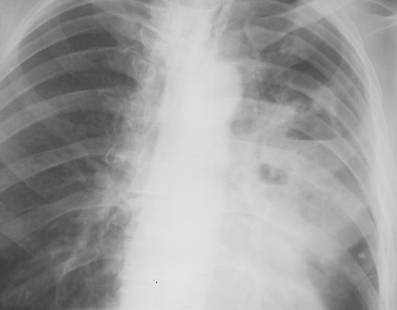

Fig. 23 – Cancer hilar stang (opacitate proximala intensa, ovalara, difuz delimitata, cu prelungiri periferice)

Cancerul bronhiilor mari (neoplasmul central) – se caracterizeaza radiologic prin:

opacitati proximale intense, ovalare, difuz delimitate, cu prelungiri periferice; pe radiografia cu raze dure se poate observa nucleul tumoral, de dimensiuni reduse, situat pe peretele unei bronhii principale;